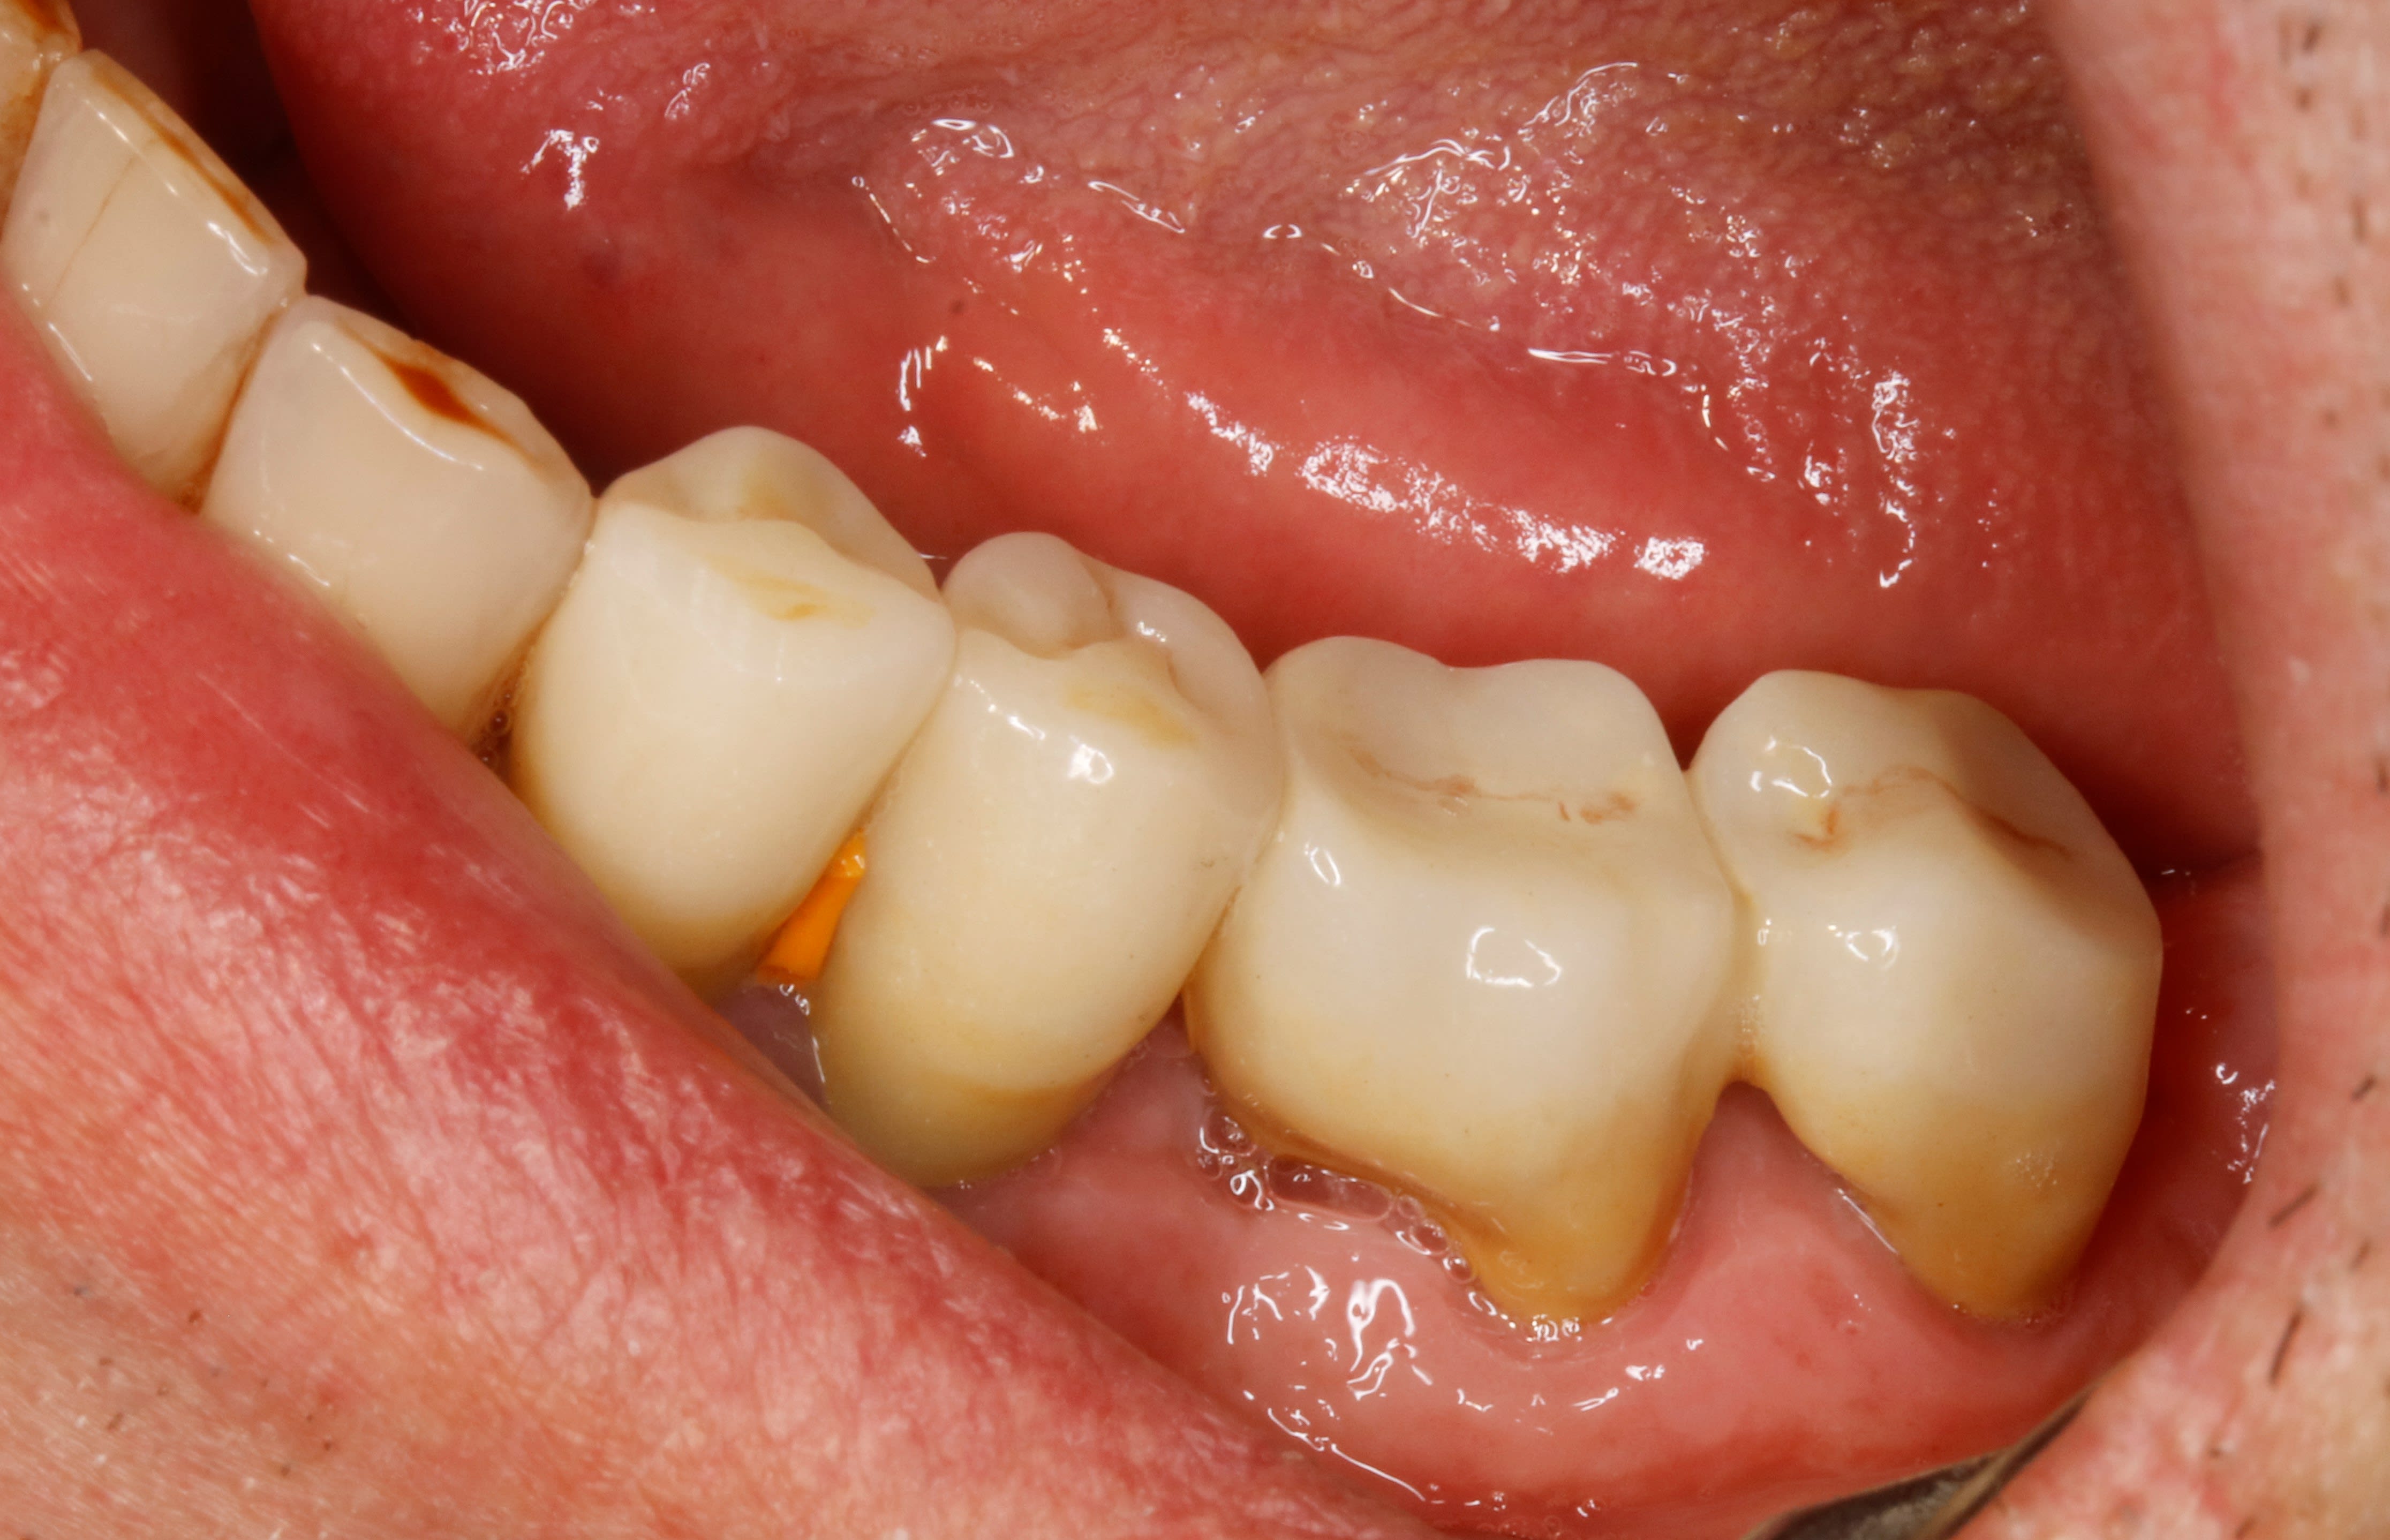

par exemple là , extraction de la vest de 36 et de la distale de 37 et hop .

Le temps de poster quelques cas, on en discute après.

Celui-ci, la racine distale de 27 a été amputée en 2012 pour raison paro, la coiffe réalisée immédiatement après sans dépose de la RCR. Elle n'est pas solidarisée à la 26.

Bridge cantilever datant de 20 ans (24) 25 26 27, lésion paro entre 26 et 27.

Découpe entre 26 et 27, amputation de la racine distale de 26, et réfection (24) 25 26.

Réalisation de 46 () 47 solidarisées, après extraction de la racine mésiale fracturée de 47; quelqu'un y avait mis un tenon, mais pas dans la distale. C'est du vice, si vous voulez mon avis.